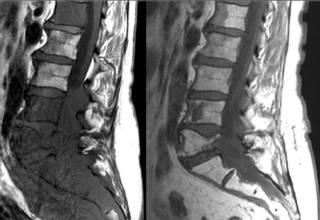

- Липома — это возникшая шишка на спине (на позвоночнике), образование которой происходит за счет жировой прослойки. Главной особенностью липомы является способность шишки перемещаться под кожей. Данное уплотнение может достигать размеров до 10 см. Во время прикосновений болезненных ощущений быть не должно.

- Атерома чаще всего появляется на позвоночнике в области шейного отдела. Образования атеромы происходит за счет скопления эпителия с секретом сальной железы. Данная опухоль не вызывает болезненных ощущений. Выявить ее можно по плотной структуре и четкому контуру. Вот как выглядит атерома (фото ниже).

- Увеличивается атерома достаточно медленно, но при ее возникновении возможен гнойно-воспалительный процесс. При попадании в шишку патогенной микрофлоры может начаться нарыв. Можно сказать, что именно открытыми воротами для инфекции и является атерома. Фото ниже показывает, как происходит борьба с атеромой медицинским способом.

Липома

Атерома

Атерома – это киста маленького размера подкожного типа, которая состоит из кожного сала. Накапливается оно в поре, постепенно растягивая сальную железу. Небольшой бугорок имеет видимые границы, обладает твердой структурой. При нажатии липому можно собрать в складку, при этом кожа приобретет синюшный оттенок, а в середине станет заметна черная точка. Размер образования может достигать 5 см и часто имеет тенденцию к увеличению в объеме. Шишка на позвоночнике может быть весьма болезненной после нагноения.

Атерома — опухоль сальной железы — может гноиться и вызывать боль